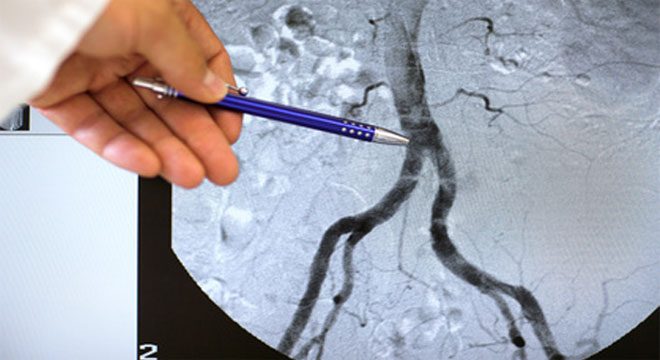

Herzkatheteruntersuchung: Darstellung der Herzkranzgefässe

• Durch den Herzkatheter wird Röntgenkontrastmittel direkt in die Herzkranzgefässe gespritzt und gleichzeitig Röntgenaufnahmen angefertigt, auf denen die mit Kontrastmittel gefüllten Herzkranzgefässe abgebildet sind (Koronarangiographie). Damit können Verengungen oder Verschlüsse exakt erkannt werden.